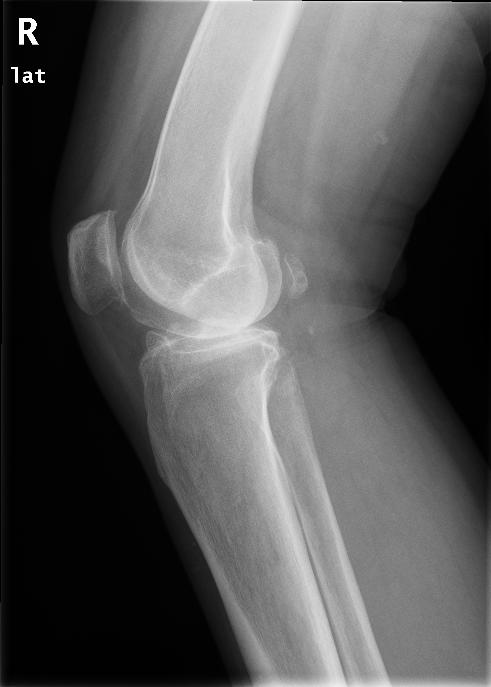

术前侧位片

患者女性,52岁,因右膝关节疼痛2月为主诉入院。入院根据病史、查体和X线片诊断为右膝骨关节炎,经常规入院检查,未发现手术禁忌症,在硬膜外麻醉下行关节镜清理手术。术中应用止血带止血,手术过程顺利,手术时间为35分钟。术后给予弹力绷带包扎右下肢,术后第一天即嘱病人下地活动,疼痛较术前明显好转。术后给予了抗生素等药物,但未应用抗凝药物。术后第三天,患者出现右下肢肿胀、胸痛、呼吸困难,经行下肢超声和肺CT检查,结合血气分析等指标,呼吸科诊断为右下肢深静脉血栓形成,肺栓塞,转入呼吸科治疗。经溶栓、抗凝、支持等治疗2周后,病情痊愈出院。出院后继续服用华法林,定期检查凝血功能,维持INR值在1.5-1.5。